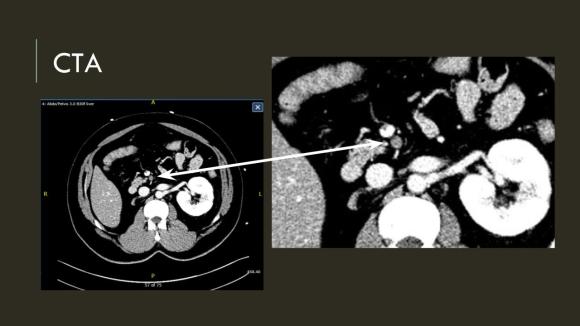

The patient is a middle aged man with risk factors of NIDDM and prior history of DVT who developed severe mid-abdominal pain at 5pm. He came to the ED at around 11pm and had a general surgery consultation who ordered a CT Angiogram showing SMA occlusion (pictured below).

Heparin was started, and at 11:30, vascular surgery was consulted. The patient had a soft, doughy texture to his abdomen, but great pain with palpation -classic pain out of proportion to the exam. Determining the patient to have acute mesenteric ischemia from a thromboembolism, I took the patient to our hybrid angiographic OR suite with the plan for arteriography, possible open thrombectomy, and exploratory laparotomy.

Arteriography from femoral access showed an occlusion of the SMA beyond the middle colic artery, a typical pattern for an embolism that occurs when embolism lodges distally and propogates proximally (image below).